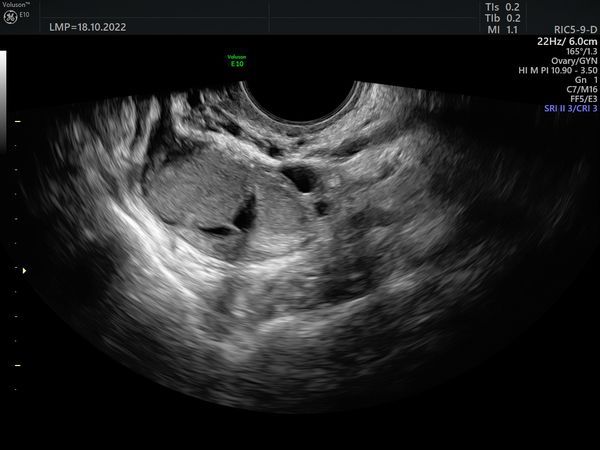

Пациентке сделали УЗИ органов малого таза на аппарате экспертного класса Voluson E 10. Согласно обследованию:

- Правый яичник. Объём 16,9 см3. Увеличен за счёт двух округлых образований с гладкими контурами. Размер первого 26 × 20 × 25 мм, объём 7 см3. Второго — 14 × 12 × 13 мм и 1,1 см3 соответственно. Содержимое образований по типу «матового стекла», акустическая тень не определяется. При цветовом доплеровском картировании (ЦДК) васкуляризация 1 балл, это значит, что образования аваскулярные (в них нет кровеносных сосудов). Количество фолликулов 8 (норма).

- Левый яичник. Объём 6,58 см3, не увеличен. Количество фолликулов 6 (норма), размер доминантного фолликула 14 мм.

Объёмных образований в малом тазу не определяется.